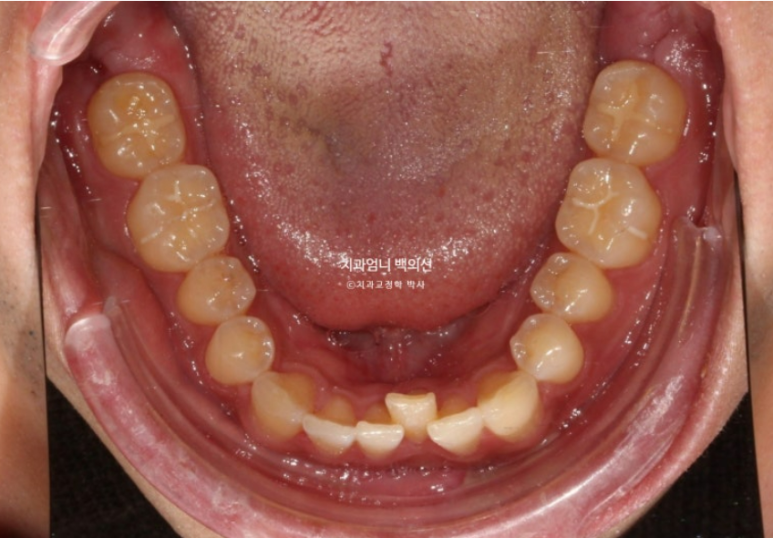

25년 2월 교정상담을 위해 오신 분입니다.

25.02

앞니가 기울어져 있고 중심선이 안 맞습니다.

어금니교합은 좋은 편입니다.

어금니 배열도 좋은 편이라 앞니 부분교정 권유드렸습니다.